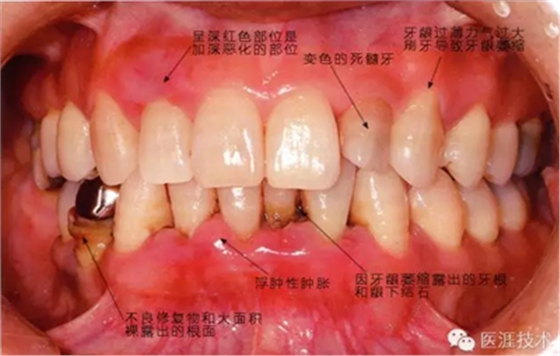

患有牙周病的牙周組織的臨床照片

56歲牙周炎男性的臨床照片

正在服用高血壓藥中的56歲男性。菌斑控制得不好。通過牙周探診,全頜有4~6mm的牙周袋,在X光片中可以看到全頜中度牙槽骨吸收,磨牙處一個地方是重度牙槽骨吸收。通過比較牙周病進展狀態(tài),邊緣部有大范圍浮腫(發(fā)紅、腫脹),和纖維性肥厚。這也可能是服用中的降壓藥的副作用導致的。因為牙齦、牙槽骨比較厚,牙齦呈架子狀。